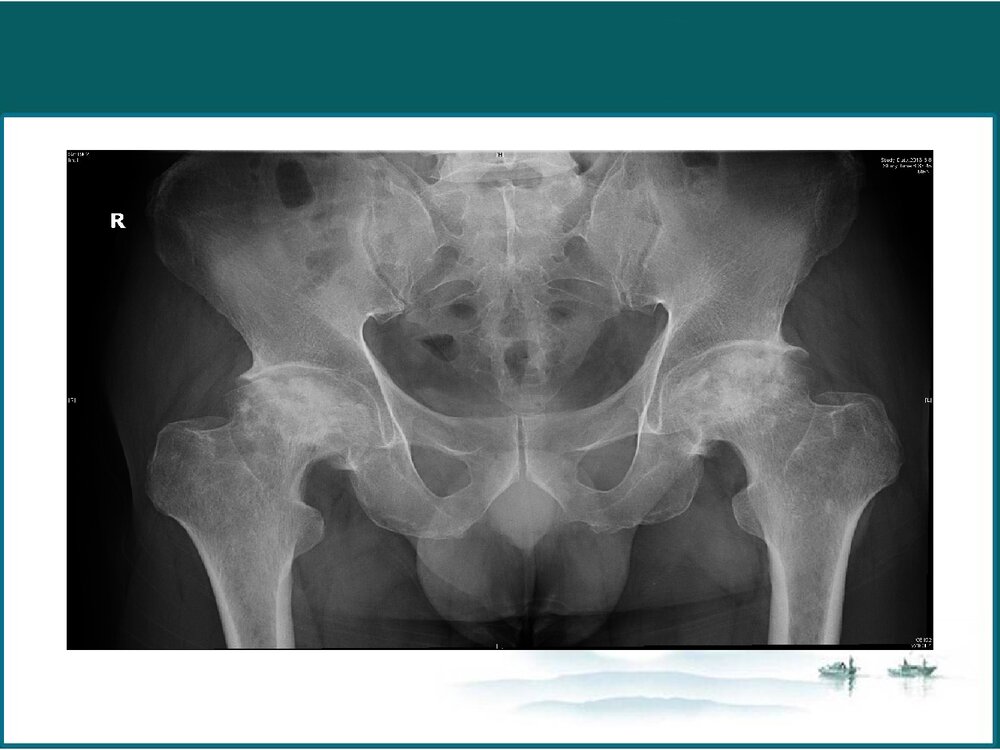

股骨头坏死股骨头坏死•燕达医院•陈明梁病历介绍患者男,52岁,因“双髋疼痛、活动障碍4年,加重1年”,门诊以“双侧股骨头坏死”收入院。患者双髋疼痛、活动受限,伸0度,屈90度,内收10度,外展10度,外旋0度,内旋0度,行走跛行。“4”字实验(+)、Thomas症(+),患者双下肢感觉正常,双足背动脉搏动好。双髋关节X线示:双股骨头坏死(Ⅳ)。病历介绍•4年前出现双侧髋关节疼痛伴有活动受限,诊断为“双股骨头坏死”,给予中药保守治疗,效果不理想。2年前患者行双髋关节血管介入治疗,术后效果可,近1年来又出现双侧髋关节疼痛不适,活动后加重,为求进一步治疗来我院。病历介绍患者否认肝炎、结核等传染病史。无药物、食物过敏史否认输血史,预防接种随当地。概述概述  股骨头坏死(ONFH)也称为股骨...